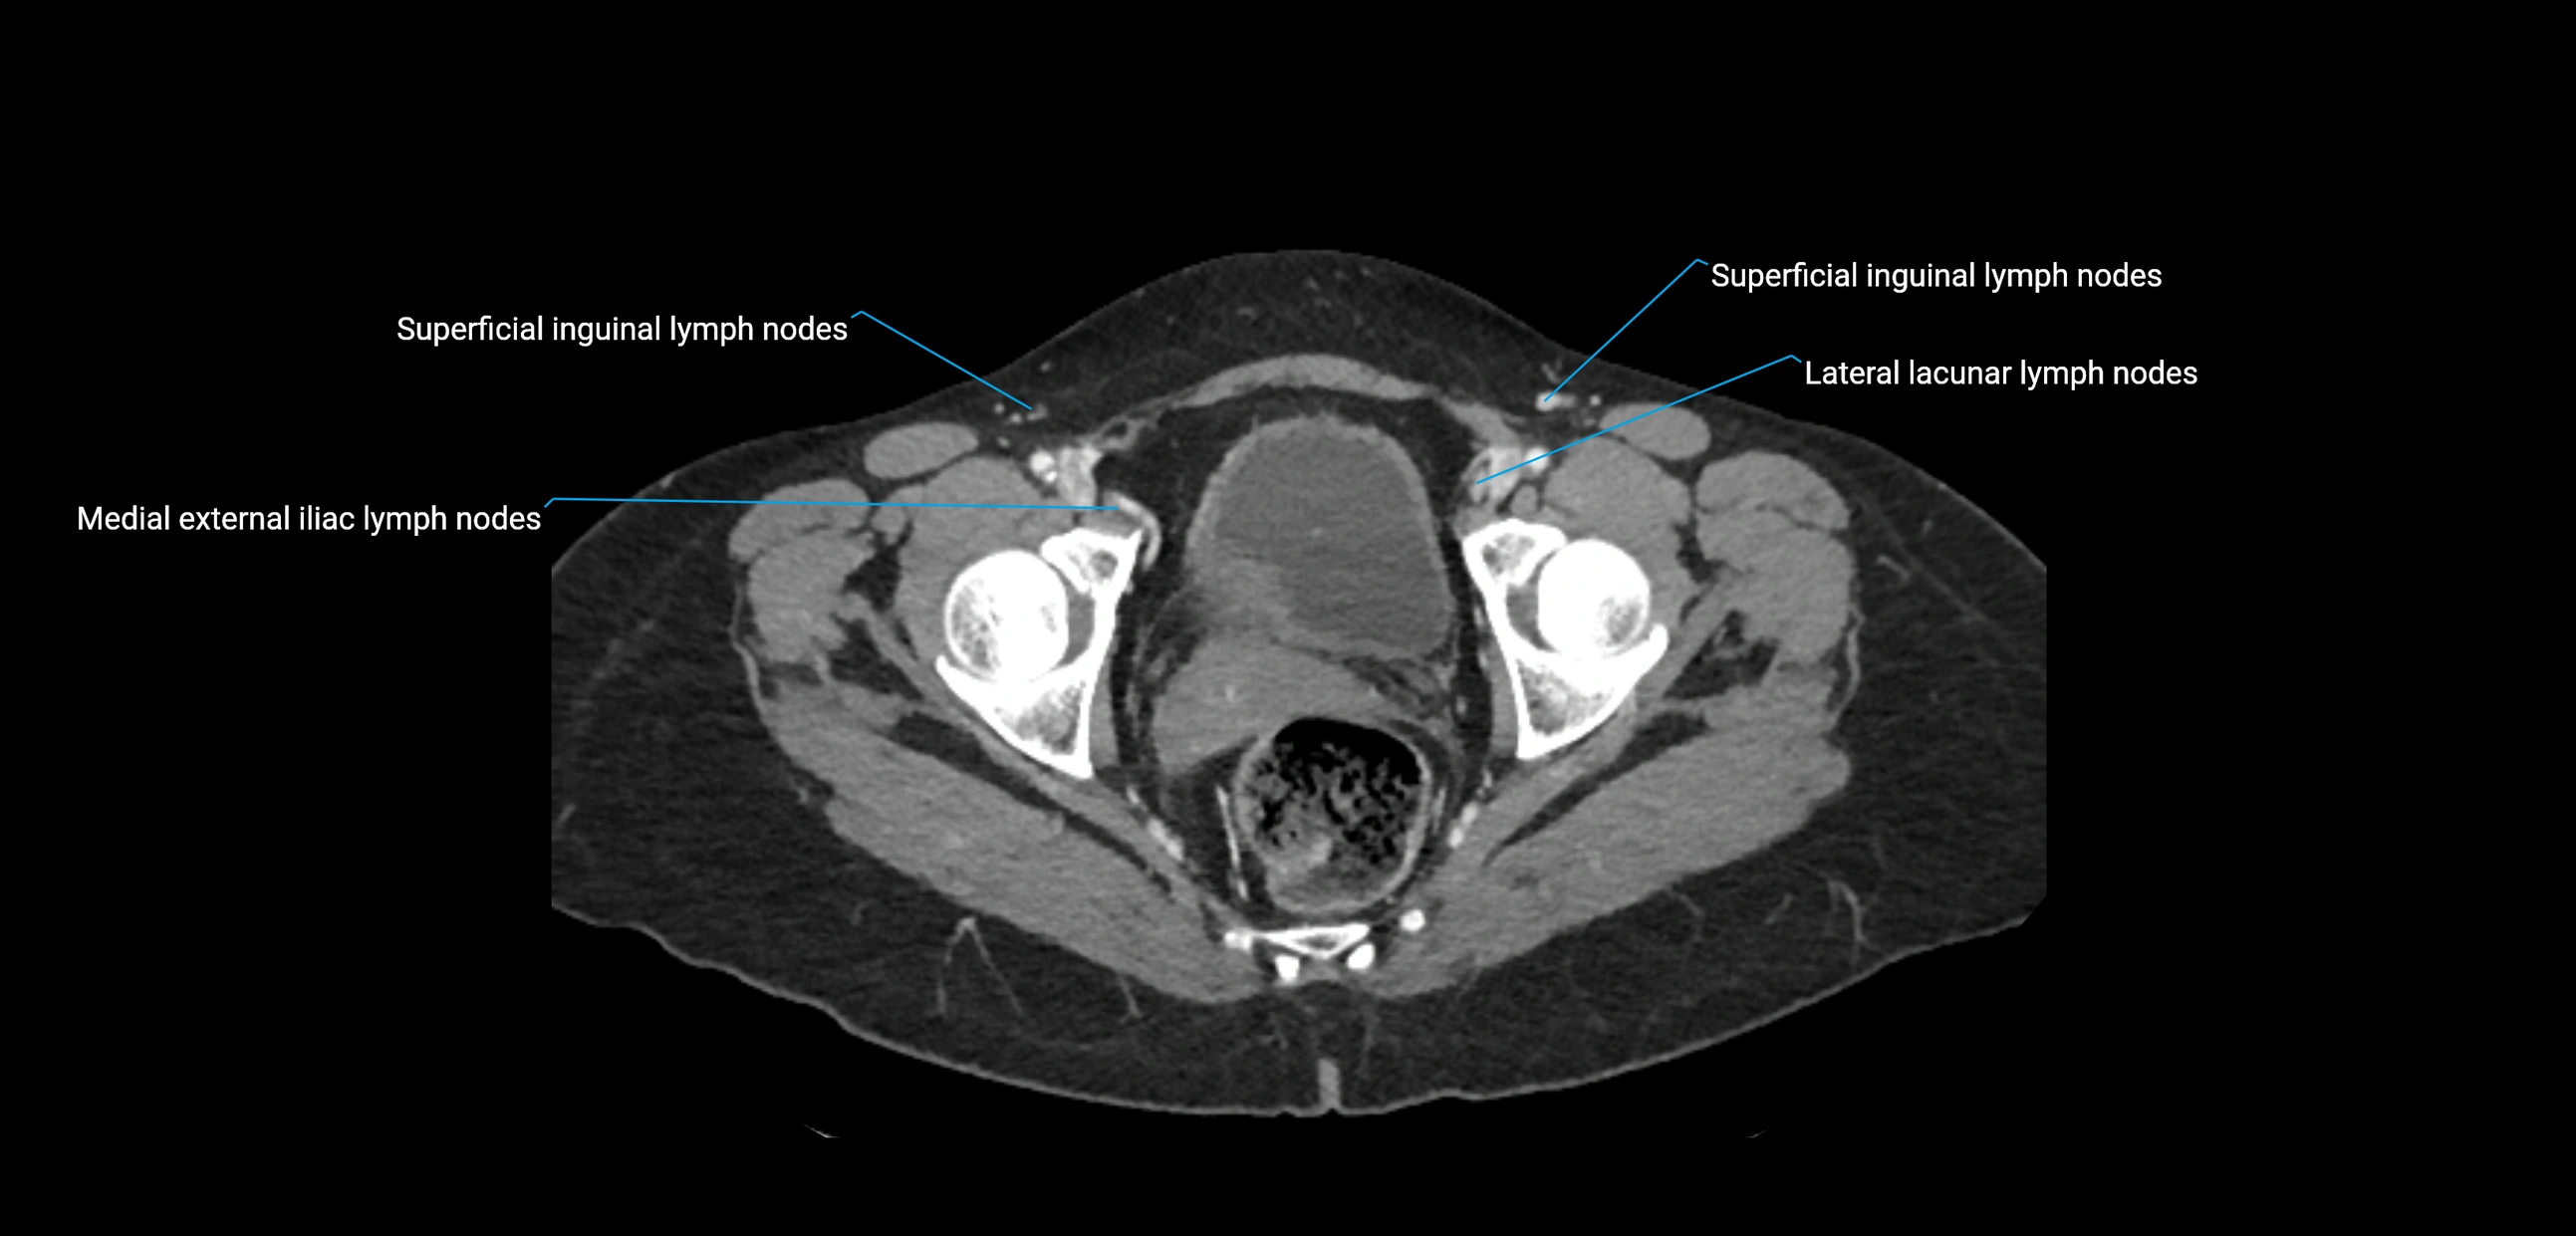

CT image

image